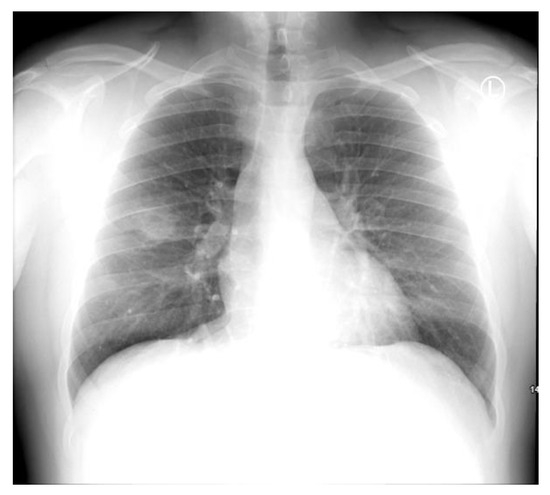

Introduction: Hafnia alvei is a Gram-negative, facultative anaerobic bacillus that is most often found as an enteric commensal. It is seldom considered to be pathogenic in immunocompetent individuals. Case report: We describe a case of a 23-year-old, previously healthy male, who presented to the emergency department with a two-day history of hemoptysis, mild dyspnea, pleuritic chest pain, fevers, and chills. Bloods revealed leukocytosis and elevated C-reactive protein. Chest X-ray and CT of the thorax revealed a cavitating lesion in the right upper lobe. He was commenced on empiric antibiotic treatment with amoxicillin/clavulanate and clarithromycin for community-acquired pneumonia in accordance with local guidelines. He subsequently underwent a bronchoscopy, and the bronchoalveolar lavage sample revealed a heavy growth of H. alvei. Despite the widely documented natural resistance of H. alvei to penicillin, the patient demonstrated complete resolution of his symptoms and initial raised inflammatory markers. Conclusions: We present a case of community-acquired cavitary pneumonia in a previously healthy young adult with H. alvei isolated from bronchoalveolar lavage samples. Parallels are drawn between our case and other cases of H. alvei respiratory isolates in our discussion of its clinical significance. Full article

Show Figures

Figure 1